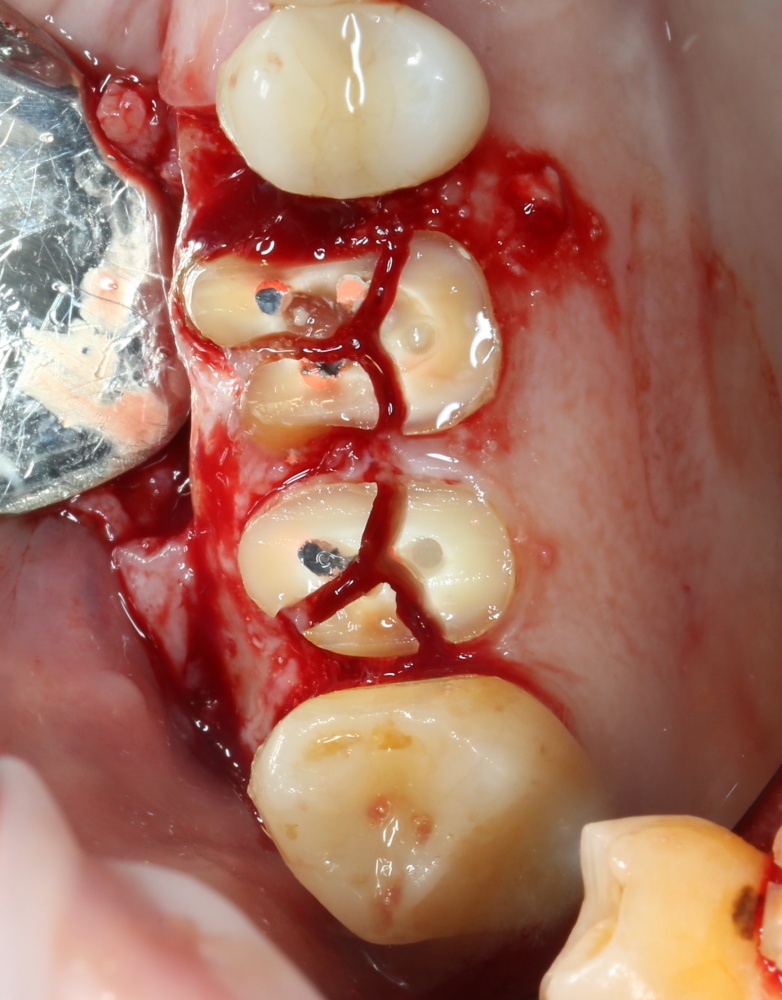

Простой синуслифтинг. Часть I.